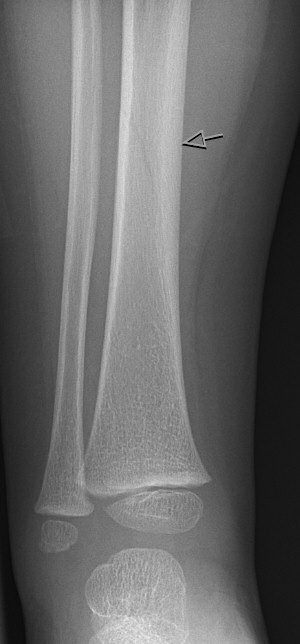

Toddler's fracture: nästan osynlig spricka (fissur) i tibiadiafys i ålder ca 9 månader - 3 år.

Toddler's fracture

Tibiafraktur hos 7-åring, behandlades med gipsstövel